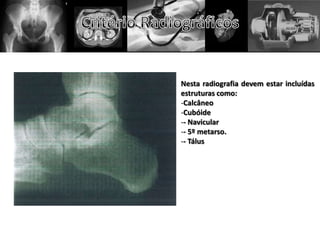

Nesta radiografia devem estar incluídas

estruturas como:

-Calcâneo

-Cubóide

-- Navicular

-- 5º metarso.

-- Tálus